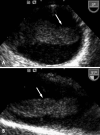

Pedunculated thrombus in the aortic arch that is associated with cerebral infarction is very rare requires prompt diagnosis and treatment to prevent occurrence of another devastating complication. Transesophageal echocardiography is useful for detecting source of embolism including aortic thrombi. The treatment options of aortic thrombi involves anticoagulation, thrombolysis, thromboaspiration, and thrombectomy. Here we report a case of huge thrombus in the aortic arch, resulting in acute multifocal cerebellar embolic infarct in patient without any risk factors for vascular thrombosis. Thrombi in the aortic arch were diagnosed by transesophageal echocardiography and treated with anticoagulants successfully.